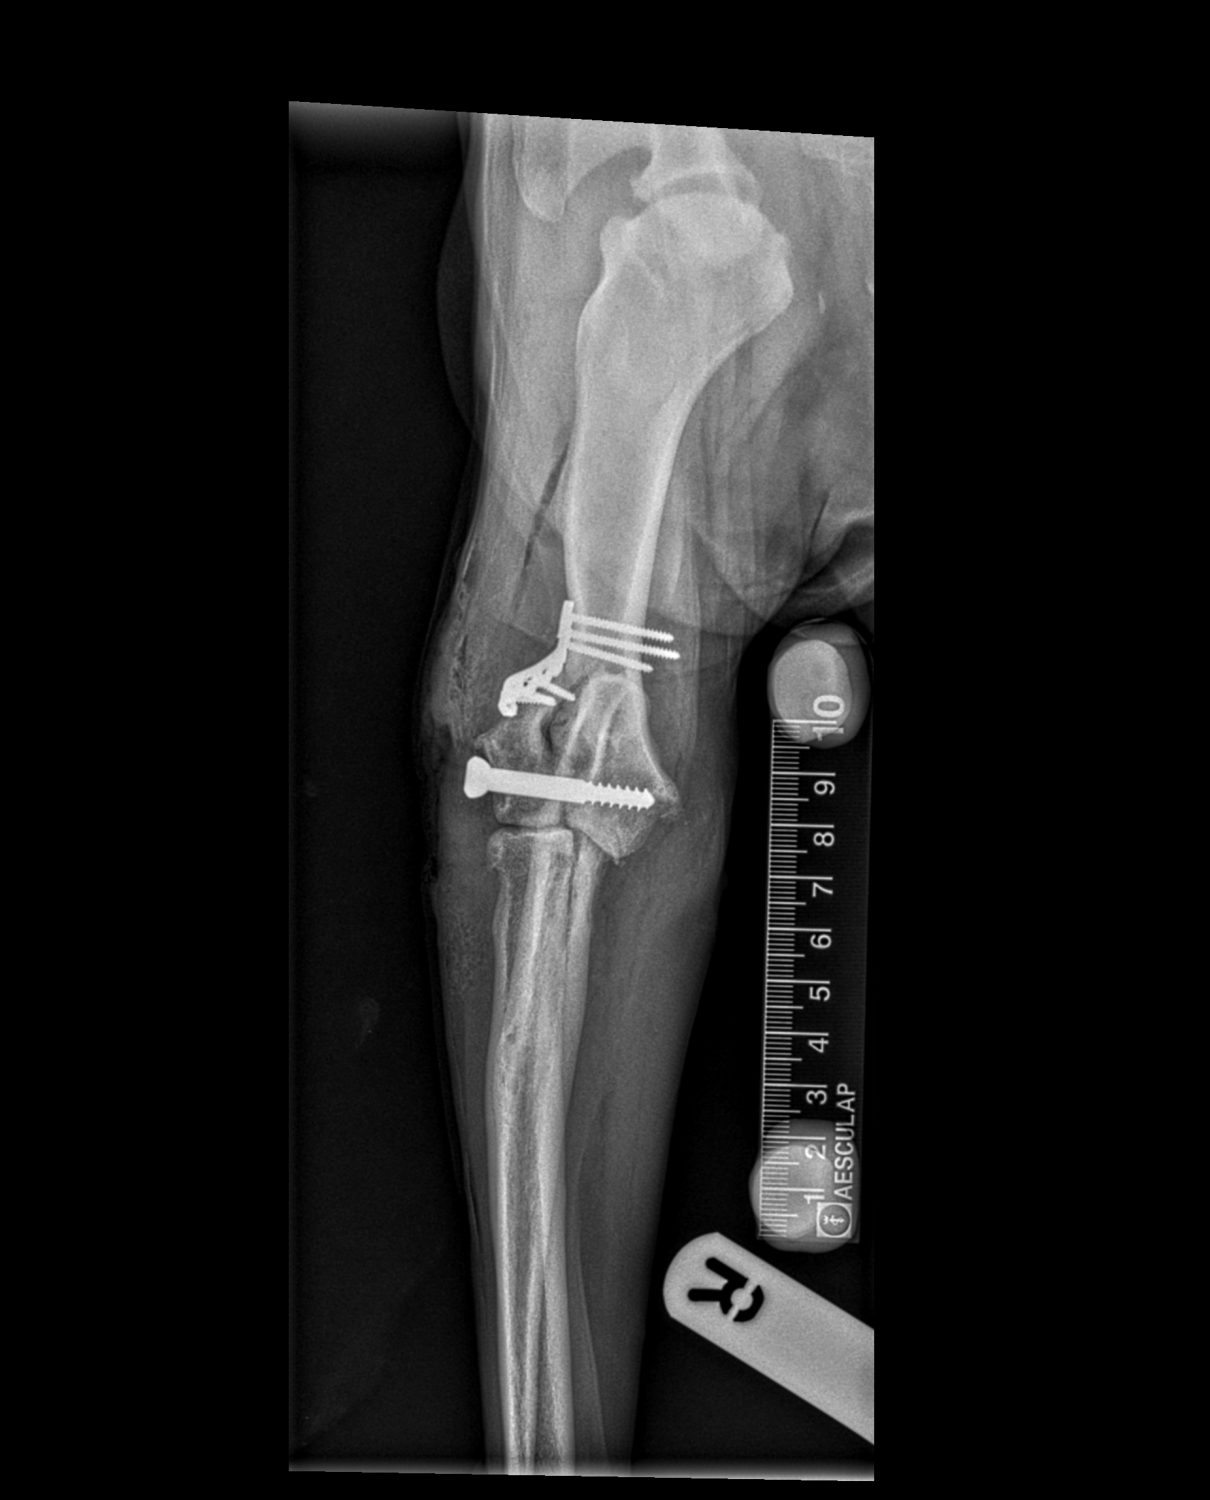

Surgical repair was required, and this was performed by practice principal Dr Martin Hobbs and senior veterinary surgeon Dr Rupert Davenport. A CT scan was carried out prior to the surgery to assist with pre-surgical planning. After incision, the fractured bone was manipulated back into a normal anatomical position, and secured in place using plates and screws. The site was closed using dissolvable sutures, and post-operative x-rays confirmed the surgery had been successful.

Chase recovered from the surgery well and he was hospitalised overnight for monitoring and pain relief. The very next day he had begun to gently place weight onto the leg and was discharged with instructions for strict cage rest and ice packing 3-4 times daily.